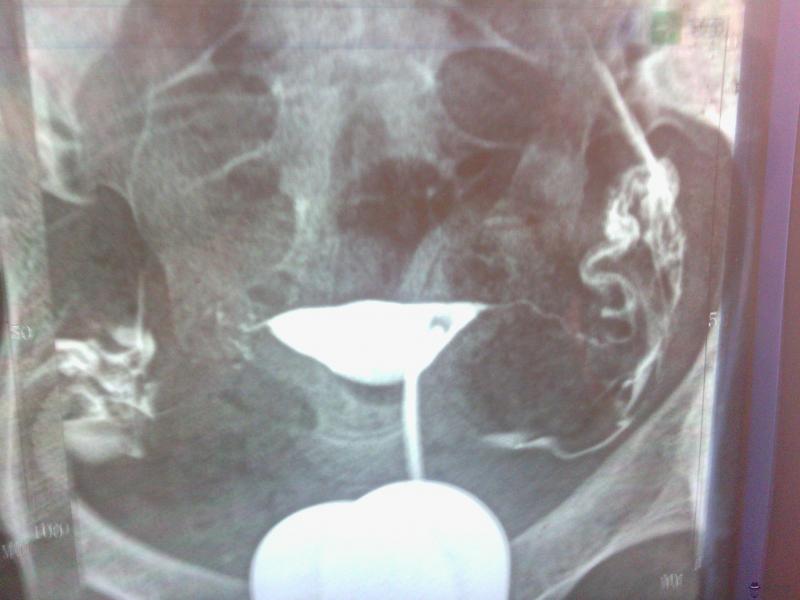

1、B型檢查:采用B型進行檢查懷孕檢查既方便,又準確,一般在5周左右就能作出診斷。B型不但能診斷正常懷孕,還可以診斷。懷孕初期癥狀小腹痛。